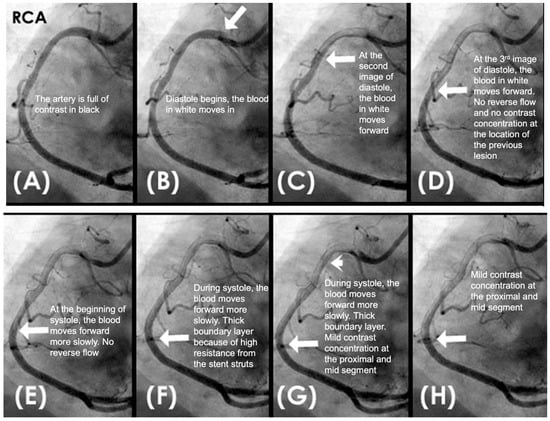

New Protocol of Coronary Images Analysis. When analyzing coronary angiographic images, it is crucial to select a projection that provides an unobstructed longitudinal view of the entire artery, free from superimposition by other arteries, branches, the liver, or shadows from spinal vertebrae. After the artery is fully opacified in black by the contrast agent, and as the contrast injection ceases while recording continues, the incoming blood appears in white as it displaces the contrast. This sequence enables the observation of flow dynamics as the blood progressively replaces the contrast agent (Figure 3A–D) [2]. By the end of the sequence, when most of the contrast has been replaced by blood, isolated pockets of contrast stagnation remain. These stagnant pockets might represent the zones and mechanism of high concentration of contrast (compression) or moderate concentration of contrast (rarefaction) as a result of passage by the water hammer-generated pressure wave (Figure 4).

IN VIVO Coronary Flow Analysis. Angiographic Compression and Rarefaction Zones. Building on an advanced understanding of pressure wave reflections in pipes from an acoustic perspective, this investigation applied acoustic principles to analyze flow dynamics in coronary arteries. The primary objective was to delineate and quantify regions within the coronary arteries characterized by pockets of high-contrast density (compression) and moderate-contrast density (rarefaction), identified as antinodes (Figure 15A,B). Conversely, areas with minimal contrast were designated as nodes. These classifications were finalized at the end of the second cardiac cycle when the contrast was almost all washed out, leaving pockets of contrast which most likely were zones of compression or rarefaction (labeled as antinodes). The needs for identifying the five zones of compression and rarefaction (antinodes) and the minimal or lesion-free segments (nodes) within a coronary artery are listed in Table 4.

The secondary objective was to examine the relationship between antinodes and the presence of coronary stenoses, as well as between nodes and minimally diseased or lesion-free coronary segments. Ultimately, the investigation aimed to establish antinodes as potential markers for high-pressure surges linked to intimal damage. These locations of antinodes are used to construct a coronary acoustic activity (or action) map, enabling the identification of existing lesions, forecasting the progression of current lesions, and predicting the development of potential future lesions. Table 5 outlines the protocol on how to identify and label the five zones of compression and rarefaction (antinodes) and the minimal or lesion-free segments (nodes) within the coronary arteries. The protocol to identify the antinodes of compression and rarefaction and the nodes in between the antinodes uses the novel coronary dynamic angiographic technique. The protocol is listed in Table 5 and Figure 16A–E.

FIRST Compression Zone with High Contrast Concentration. Angiographic Identification. During diastole, coronary blood flow reaches a relatively high velocity. At the onset of systole, the contraction of the left ventricle abruptly interrupts this flow, triggering a water hammer effect. This results in the formation of a retrograde pressure wave, which collides with the antegrade flow at a critical timing when diastole transitions into systole. The initial reflection point, designated as location 1, is characterized by pockets of prolonged concentration of contrast agent, seen as a disorganized mixing of dark (contrast) and light (blood) materials (blue arrow in Figure 16E). These black-and-white pockets may signify turbulent flow, mirroring the surge of pressure in the local area (Figure 16A–D).

Mechanism of Damage. At location 1, damage mechanisms are likely driven by localized pressure spikes, stress concentrations, or repeated high-pressure cycles (vibrations), which induce deformation, cracking, or microtears in the intimal layer. These disruptions facilitate the migration of low-density lipoprotein (LDL) cholesterol into the subintimal space, initiating the atherosclerotic cascade (blue arrow in Figure 16E).

Clinical Relevance. The lesion at this location is very important because this is the most common lesion in the right coronary artery (RCA) and the most common location for ST elevation myocardial infarction in the RCA [35]. The reason is because this is the location where the pressure wave from water hammer hits first in its retrograde reflection, when diastole transitions to systole.

CRITICAL THINKING. High Concentration of Contrast at location 1 as a Marker of Compression Activity. During a typical cardiac cycle, antegrade blood flow accelerates during diastole and transitions rapidly into the systole, initiating a water hammer phenomenon that generates a retrograde pressure wave. This retrograde wave propagates at nearly the speed of sound and undergoes multiple reflections within one or two diastole–systole cycles along the length of a coronary artery. These reflections produce hundreds of retrograde pressure waves, which may synchronize with antegrade waves to form resonant patterns or, conversely, cancel out. The wave reflections occur at distinct locations: the diastole-to-systole junction (location 1), the coronary artery ostium (location 4), and the systole-to-diastole junction (location 2). The resulting wave dynamics display features of acoustic resonance, with regions of high contrast concentration corresponding to antinodes—pressure peaks associated with arterial damage or the progression of atherosclerosis (Figure 16E). High-contrast regions at locations 1 and 4, observed in coronary angiography, likely represent zones of compression and rarefaction, indicative of pressure surges that may compromise the intimal layer. The critical challenge lies in determining how these observations and hypotheses can be rigorously validated.

SECOND Rarefaction Zone with Moderate Contrast Concentration Angiographic Identification. Analogous to the retrograde propagation of a pressure wave caused by a water hammer toward the open end of a tube, when a high-density (compression) pressure wave reaches the ostial segment of a coronary artery—serving as an open interface—and contrast briefly displaces outward to equilibrate the pressure between the coronary artery and the aortic root. This displacement induces a localized pressure drop at the point of reflection. The resulting low-pressure zone, or rarefaction, propagates retrogradely through the coronary artery as a reflected rarefaction pulse (Figure 8 and Figure 17A–D). This phenomenon constitutes the second reflection point, labeled as 4 in Figure 16E, corresponding to the distal open end of the coronary artery, which is conceptualized as a tubular structure.

THIRD Rarefaction Zone with Moderate Contrast Concentration. Angiographic Identification. At the onset of the cardiac cycle, antegrade flow is initiated during diastole. During systole, the contraction of the left ventricle generates a pressure wave, characteristic of the water hammer effect, which propagates retrogradely and impacts the leading edge of the antegrade flow, causing intimal injury at this location (labeled 1) where diastole transitions to systole. This pressure wave continues its retrograde propagation, ultimately reaching the ostium of the artery, identified as location 4. Simultaneously, coronary flow advances forward during systole, albeit at a reduced velocity. Upon the end of systole, diastole resumes. The transition point where coronary flow shifts from systole to diastole is identified as location 2 where the elevated systolic pressure gives way to the lower diastolic pressure.

Mechanism of Damage. At position 2, during the shift from systole to diastole, the interaction between the water hammer reflection wave and a region of reduced pressure induces a transient local pressure disturbance and generates a chaotic pressure gradient. This disruption accelerates particle motion within the flow, producing abrupt velocity fluctuations. These conditions foster turbulence, marked by irregular and chaotic particle trajectories, particularly when the interaction induces flow separation or intensifies shear stress along the vessel wall. The ensuing turbulence compromises the endothelial lining, serving as a catalyst for the initiation of the atherosclerotic cascade. However, because this is a transition from high pressure to lower pressure, the turbulence is not as powerful as in location 1, where the low pressure of diastole meets the high pressure of retrograde systole. As a result, the lesion at location 2 is not as severe as the one at location 1 (Figure 16E).

FOURTH No Lesion ZONE in the NODES. In theory, the zones of nodes in a water hammer event experience minimal stress compared to the zones of antinodes, as nodes are characterized by stable pressure points with little fluctuation. These areas generally serve as neutral zones where the destructive effects of pressure surges are negligible. Since there is no significant pressure surge or high shear stress at the nodes, they are typically not sites of damage. Therefore, in the zones of these nodes, no stenosis or only minimal plaques or calcification with minimal lesion are identified (Figure 18C,D).

CRITICAL THINKINGS. Pressure Surge and Mechanism of Damage. When a pressure wave propagates through the blood of a coronary artery, it generates alternating regions of particle compression and rarefaction. At compression points (e.g., locations 1 and 3), there is a high concentration of contrast, whereas at rarefaction points (e.g., locations 2 and 4), the contrast concentration is less intense.

At location 1 with compression, corresponding to a pressure crest, the low-pressure antegrade flow during diastole is rapidly overtaken by a high-pressure surge during systole, producing a pronounced pressure peak. This abrupt surge induces disruption of the intima and increases the likelihood of severe damage leading to more severe lesions, plaque rupture, and the onset of acute coronary syndrome (ACS) (Figure 18A)

In contrast, at location 2 with rarefaction, representing a pressure trough, the transition de-escalating from high-pressure systolic flow to lower-pressure diastolic flow results in a pressure nadir. Unlike location 1, the absence of substantial pressure surges at location 3 generates minimal turbulence, causing less intimal damage. As a result, lesions in these regions are less severe, and the risk of triggering ACS is comparatively lower. Furthermore, the pressure surge within the very short artery remains limited due to the short distance, preventing the accumulation of sufficient pressure momentum (Figure 18A,B).

At nodal points, where pressure fluctuations and particle motion are minimal, the lack of significant dynamic stress inhibits lesion formation and progression. Consequently, these nodal segments exhibit minimal or no lesions (Figure 18C,D).

Coronary Acoustic Action MAP. The coronary flow investigations based on acoustics pinpointed pockets of high- or moderate-contrast concentrations, which might correspond to compression and rarefaction zones, respectively. Compression antinodes, linked to severe stenotic lesions, were believed to be due to rapid shifts from low-pressure diastolic flow to high-pressure systolic surges, causing turbulence and intimal disruption. Rarefaction antinodes, associated with milder lesions, were believed to be due to de-escalating transitions from high systolic pressure to lower diastolic pressure, resulting in less turbulence and milder injury. Nodes remained unaffected because there was no disorganized flow in its segments. An acoustic action map based on antinode and node locations could facilitate identifying current lesions and predicting future ones (Figure 19).